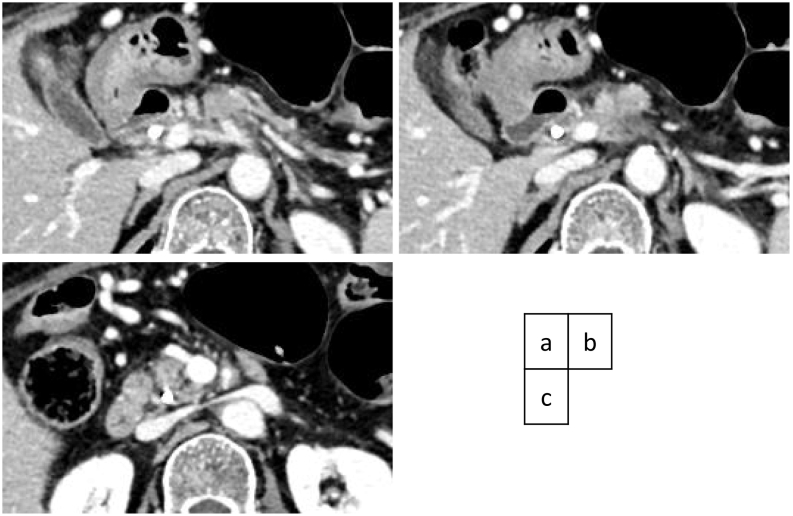

A weekly doublet chemotherapy with 1000 mg/m2 of gemcitabine and 125 mg/m2 of albumin-bound paclitaxel for three to four weeks was started 40 days after the first visit to our hospital. Because the patient suffered from grade 4 neutropenia after the first two administrations during the first cycle of the doublet regimen, the dose was set at 70% of full dosage and was administered two to three weeks. The effect of chemotherapy was estimated by a monthly evaluation of tumor markers and CT scan every four months. The tumor shrunk on each imaging evaluation during chemotherapy, with residual periarterial high-density area around the CA and proximal SMA (Fig. 3a,b,c). After 11 cycles (231 days) of chemotherapy with 60% relative dose intensity, the patient was referred for surgery. As the edge of the shrunk tumor appeared to regress apart from the CBD, the internal stent tube was removed one month prior to surgery.